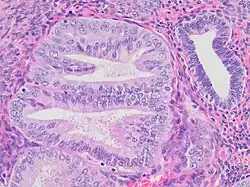

- Architectural gland crowding

- Altered cytology relative to background glands

- Minimum size of 1 mm

- Exclusion of adenocarcinoma

- Exclusion of mimics

Mitoses should also preferably be seen. Compare to normal endometrial gland at right.